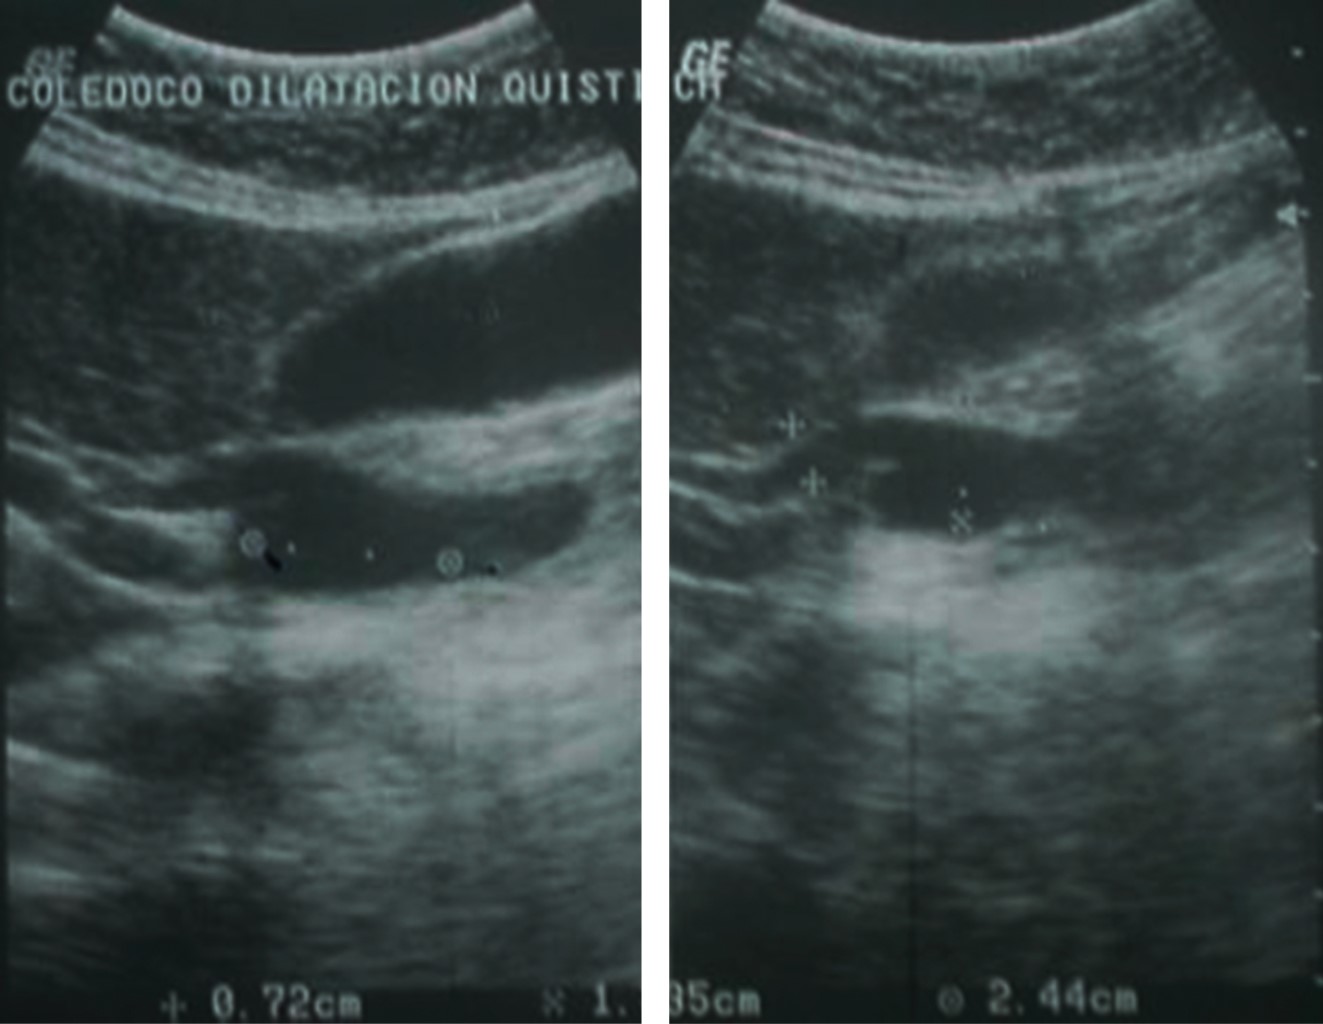

Another ultrasonographic study was performed as an outpatient that showed a normal liver, an anechoic gallbladder measuring approximately 6.3 × 3.1 cm with a thickness wall of 4 mm, and the presence of a common bile duct cyst in the distal region measuring 1.35 × 2.4 × 0.72 cm (Figure 3). The common bile duct was of normal caliber in its proximal segment with well-delimited edges without significant compression of neighboring organs.